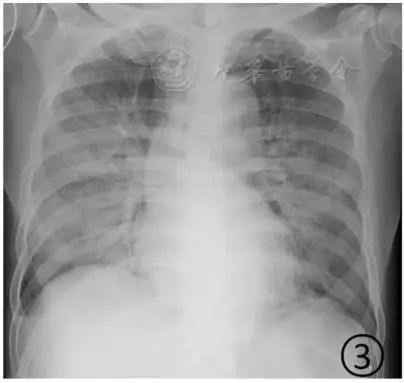

正常的肺片图片大全

正常的肺片图片大全,皮试不正常的图片